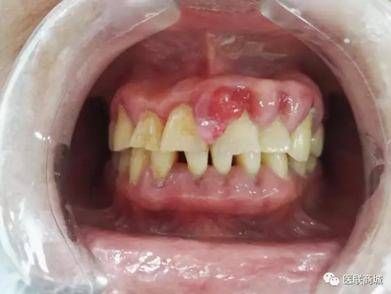

口腔衛(wèi)生狀況較差,牙石(++),軟垢(++),全口牙齦紅腫增生明顯,11、21、22、23牙齦增生明顯,11、21齦乳頭呈菜花樣增生,質軟,界清,觸痛(-),易出血,全口PD=5-7mm,下前牙舌側GR=1-2mm,咬合關系基本正常,未見明顯咬合創(chuàng)傷。